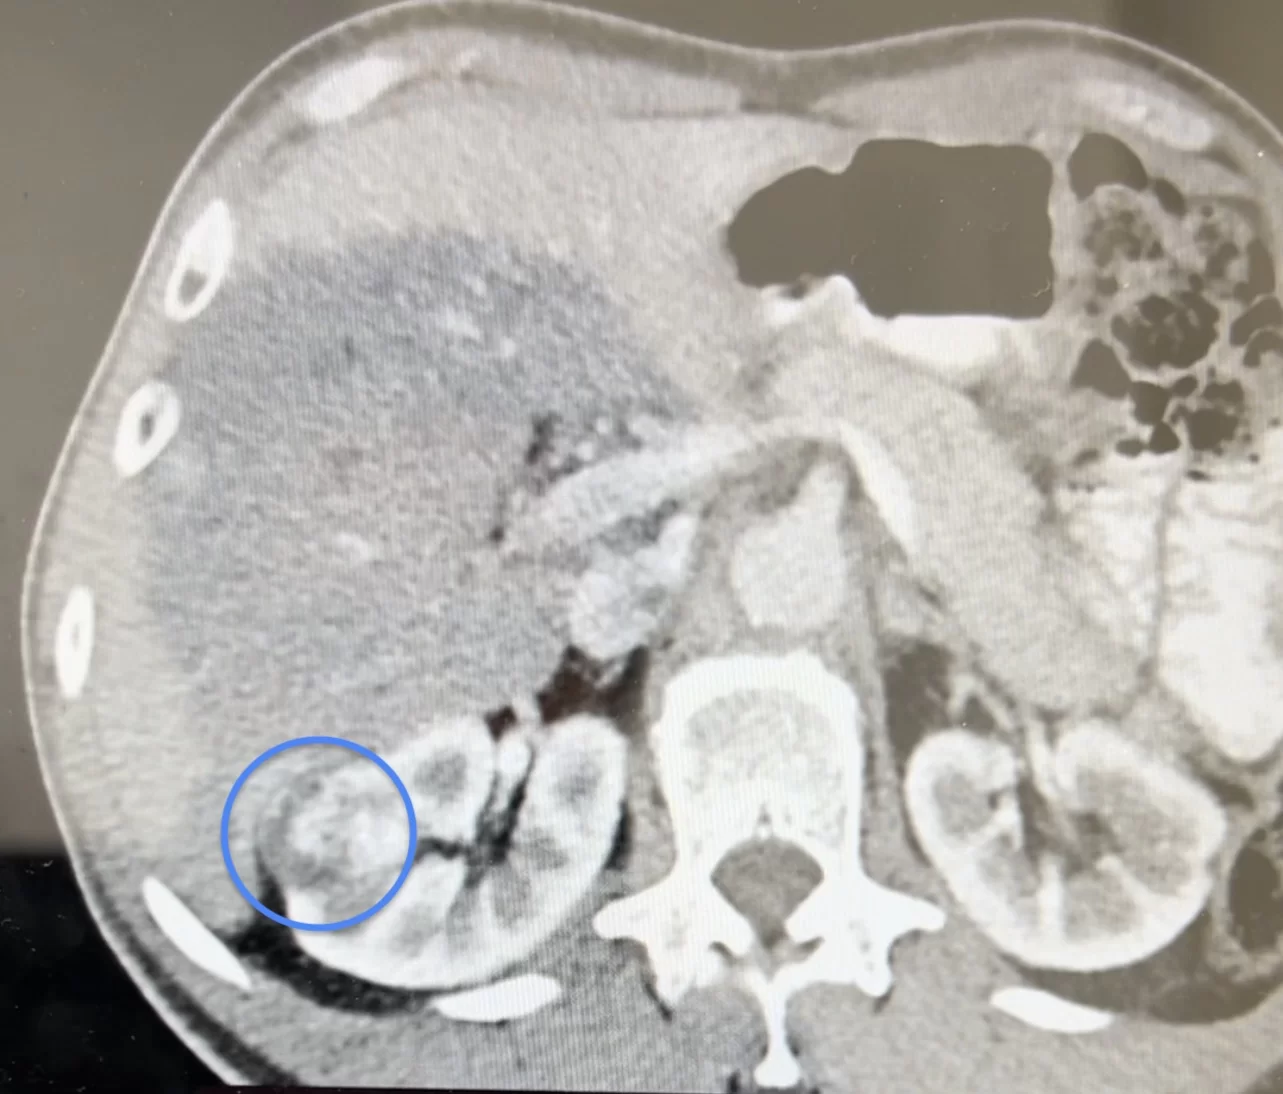

Ασθενής με όγκο νεφρού διαστάσεων 2,5 cm αντιμετωπίστηκε με μεγάλη επιτυχία από τον Dr. med. Βασίλειο Γκολεζάκη και την ομάδα του. Ο όγκος ήταν στην έξω επιφάνεια της μεσότητας του δεξιού νεφρού, μεικτής υφής (κυστικά και συμπαγή στοιχεία) και σε επαφή με περιφερικούς κάλυκες στη μέση καλυκική ομάδα του δεξιού νεφρού.